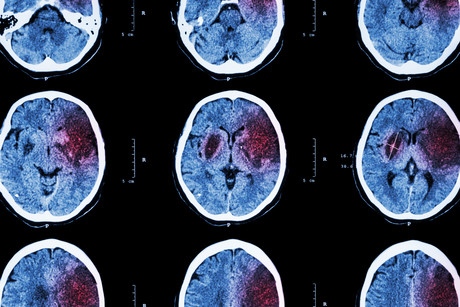

The study found that the most common type of stroke was haemorrhagic stroke (burst blood vessel). These cases were also documented to involve other illicit and licit psychostimulants. In no case was medication for attention deficit hyperactivity disorder identified.

Significantly, the anatomical location in which strokes occurred differed between psychostimulant users and others, said Professor Darke. Psychostimulant-related strokes were more likely to occur in the substance of the brain itself (intracerebral), rather than the space surrounding the brain. These types of strokes are far more likely to be fatal, he said.